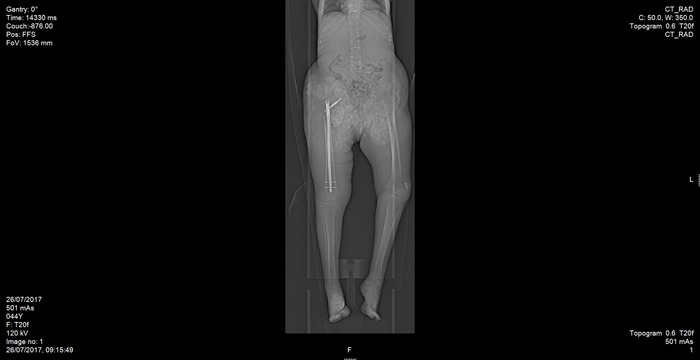

Figure 2.

Post-operative CT Scan.

During the operation, periarticular calcium deposits made the visualization under X-ray fluoroscopy impossible. Therefore, debulking, open reduction, and internal fixation were mandatory.